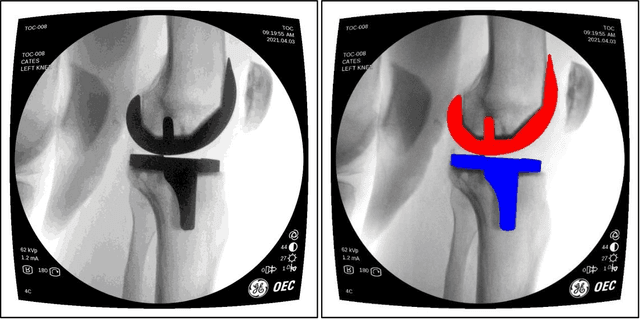

Abstract:Image segmentation in total knee arthroplasty is crucial for precise preoperative planning and accurate implant positioning, leading to improved surgical outcomes and patient satisfaction. The biggest challenges of image segmentation in total knee arthroplasty include accurately delineating complex anatomical structures, dealing with image artifacts and noise, and developing robust algorithms that can handle anatomical variations and pathologies commonly encountered in patients. The potential of using machine learning for image segmentation in total knee arthroplasty lies in its ability to improve segmentation accuracy, automate the process, and provide real-time assistance to surgeons, leading to enhanced surgical planning, implant placement, and patient outcomes. This paper proposes a methodology to use deep learning for robust and real-time total knee arthroplasty image segmentation. The deep learning model, trained on a large dataset, demonstrates outstanding performance in accurately segmenting both the implanted femur and tibia, achieving an impressive mean-Average-Precision (mAP) of 88.83 when compared to the ground truth while also achieving a real-time segmented speed of 20 frames per second (fps). We have introduced a novel methodology for segmenting implanted knee fluoroscopic or x-ray images that showcases remarkable levels of accuracy and speed, paving the way for various potential extended applications.